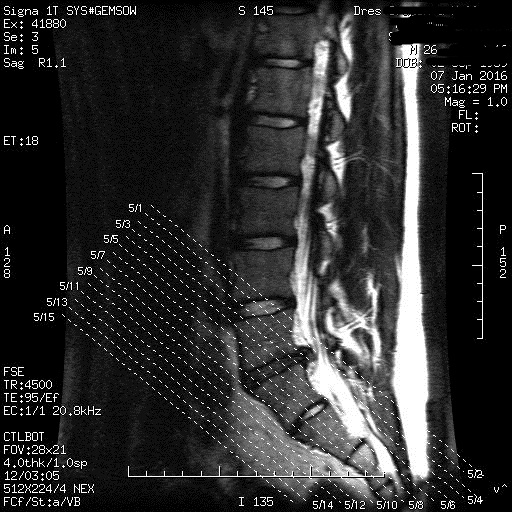

Ebenso war ich heute bei einem 2. Doc welcher mir das ganze hinten mal mit dem Kinesiotape zugekleistert hat und mir eine Überweisung für das MRT sowie ein Muskelentstannendes Mittel gegeben hat. Der Arzt war nur ein Allgemeinmediziner und ist bei weitem nicht so in der Materie drin wie ein Orthopäde oder Chrio aber er meinte, dass momentan keine Blockierung vorliegt - deswegen gehe ich weiterhin davon aus das Durch die lange Blockade der Ischias gereizt/entzündet ist.

Habe gestern auch Muskelrelaxanzien verschrieben bekommen, die nehme ich jetzt in Verbindung mit Diclo. Im Januar steht dann MRT an...

Bei solchen Beschwerden wäre es vielleicht mal garn nicht verkehrt ein MRT zu machen um ein Bandscheibenvorfall/Vorwölbung auszuschließen....

Da sich nach der anfänglichen Diagnose einer ISG Blockade die Beschwerden nicht besserten - war mein erster Weg, der Weitere zum Doc, um mit Maßnahmen wie Krankengymnastik anzufangen und das Ganze mit einer Schmerzmitteltherapie zu ergänzen. Da sich aber nicht gleich der Erfolg einstellte wie ich erhoffte, ging ich also wieder zu dem netten Herren und lies mir eine Überweisung zum MRT geben - dies nur zu deiner Info um deine Grundkenntnisse zu diesem Thread ein wenig auf Vordermann zu bringen

War heute beim Orthopäden gewesen, ist wie ich vermutet hatte ein bandscheibenvorfall...

Die daraus resultierenden schmerzen bringen mich ein eine schonhaltung und diese führt zu muskelverkrampfung/-härtungen und diese wiederum lassen ständig das ISG blockieren - Teufelskreis.